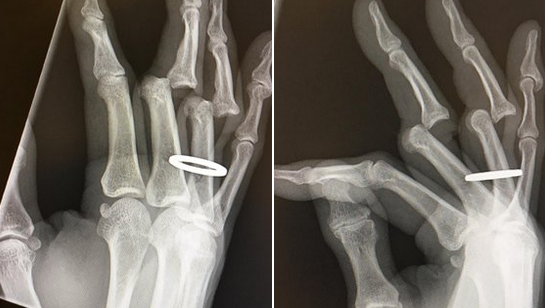

Az 52 éves gördeszka-sztár ugyan a világ legdurvább deszkás trükkjeit is rutinnal csinálja, de most egy elég ronda balesetet kellett átélnie.